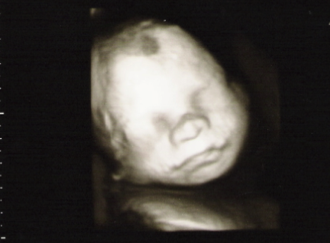

Erstes CTG - Tagebücher aus der Schwangerschaft von Ingrid aus Hürth